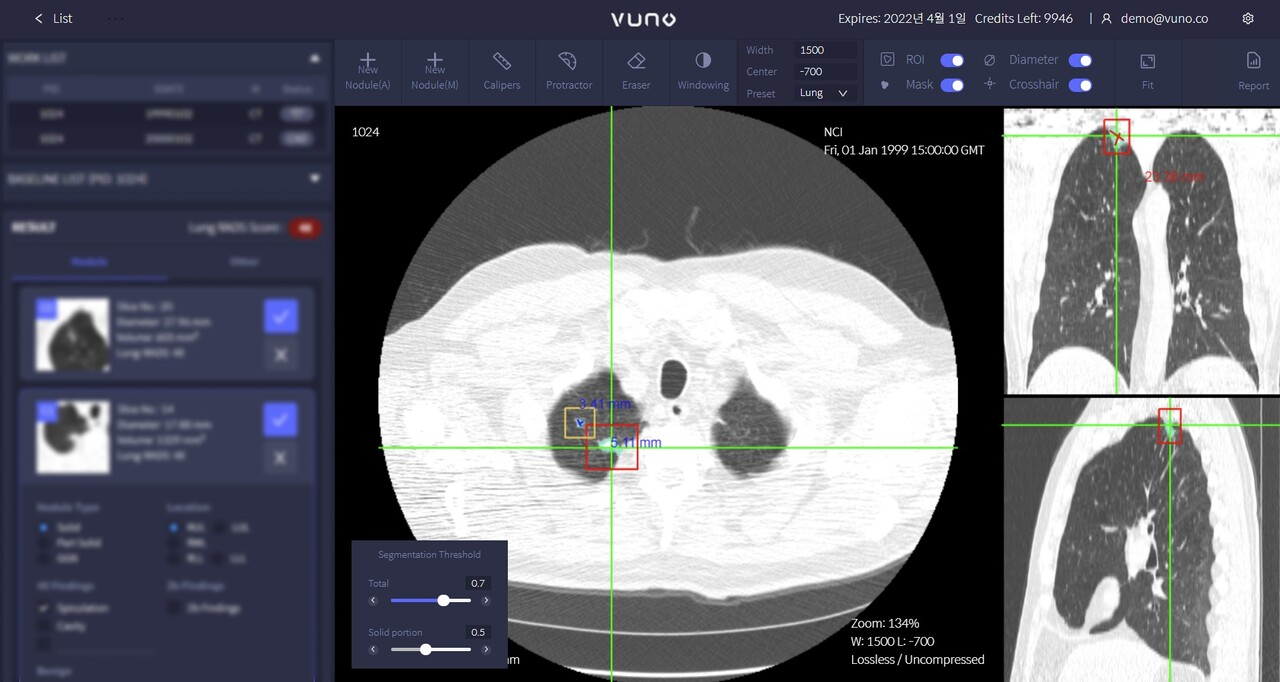

LungCT AI